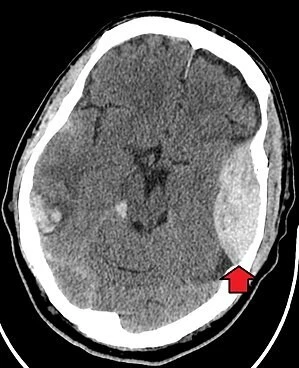

한 소년이 사고로 인해 죽음에 이르는 모습에서 우리는 고대 그리스 시대의 외상 치료 개념에 대한 한계를 엿볼 수 있습니다. 실제적으로 머리에 심한 외상을 당했을 때, 밖으로 흐르는 피보다는 보다는 두개골 내 출혈에 의해 사망에 이르게 됩니다.

아폴론이 히아킨토스의 이마에 흐르는 피를 지혈했다고 해도, 그의 두개내 출혈을 치료하지 못한다면 결국 사망에 이를 수밖에 없다는 것이죠. 히아킨토스처럼 두부의 외상이 발생한 이후 단시간 내에 사망에 이르렀다면 엄청난 양의 경막외출혈(epidural hemorrhage, EDH)이 발생했을 가능성이 높았을 겁니다.

경막외출혈은 현대에도 실제 교통 사고나 폭행과 같은 직접적인 외상에 의해 발생하며, 단시간 내에 의식을 잃거나 반신 마비, 혼수 상태와 같은 신경학적 증상이 나타나다 사망에 이를 수 있는, 매우 위험하고 응급한 질환입니다.

경막외출혈.jpeg 경막외출혈의 CT 사진 소견. 붉은 색 화살표가 가리키고 있는 곳에 피가 고여 있으며, 이로 인해 뇌가 반대편으로 밀리고 있습니다.

현대 의학에서는 이러한 증상이 있을 때 뇌 컴퓨터 단층 촬영(Computed tomography, CT)으로 병변을 확인하고 응급 수술을 시행하게 됩니다. 히아킨토스도 현대 의학에 의한 적절한 치료를 받았다면 꽃으로 변하는 대신에 그 생명을 이어갔을지도 모를 일입니다.